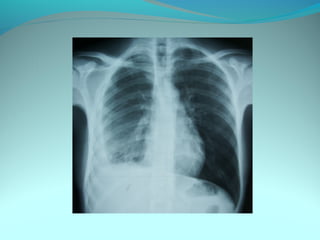

Opacité occupant la partie externe du 1/3 infer du poumon droit

dense et homogene ovalaire de 8cm de grand axe vertical

La limite externe se confend avec une opacité d’environ 1cm comble

les coupole costodiaphragmatique droit

Limitée a sa partie sup par la petit sessure qui est epaisse et pas de

lyse costale

 DIAGNOSTIC :DIAGNOSTIC :

 1_1_cancer bronchique droit( d epaississement)

 2_2_ kyste hydatique au stade sain